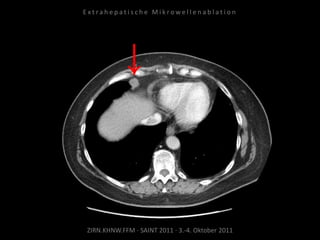

Patient: Weiblich, 71 Jahre

Diagnose: Ovarial-Ca,

größenprogredienter Lymphknoten

zwischen Herz und Leber als einzige

Metastase.

Ausgangsbildgebung:

CT vom 16.08.2010

Bildgebung vor MWA:

CT 14.03.2011

Situation:

Nur 1 Metastase, diese ist jedoch

progredient. Kritische Lage in

Herznähe.

Ziel:

Destruktion der solitären Metastase

unter Schonung der Nachbar-

strukturen.

Indikation zur MWA:

Nachweis nur einer Metastase, diese

ist progredient, in der Größe gut zur

Ablation geeignet.

Ablation am 24.03.2010:

2 Nadelpositionen.

Kontrolle:

MRT 05.04.2010

Kein weiteres Wachstum.